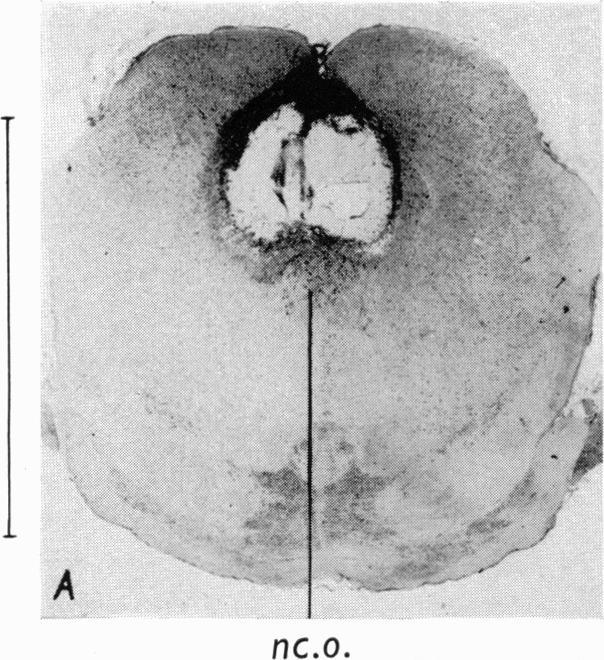

Organization of the subcortical system governing defence and flight reactions in the cat.

J Physiol. 1962 Feb;160(2):200-13. doi: 10.1113/jphysiol.1962.sp006841.